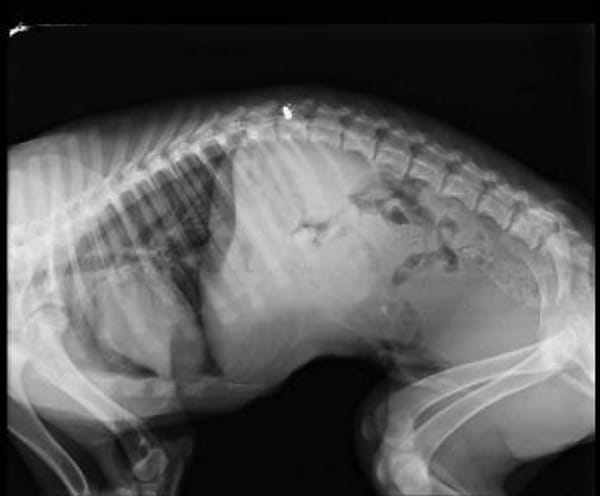

▪ Handicap: Querschnittsgelähmt

Paris war gerade einmal wenige Monate alt, als sein Besitzer ihn auf grausame Weise erschießen wollte. Er überlebte schwer verletzt und schleppte sich mit seinen Wunden durch die Berge im Norden Griechenlands, bis er gefunden wurde. Das öffentliche Tierheim war keine Option und auch die Tierschützer vor Ort konnte ihn nicht lange unterbringen. Zu seinem Glück wurde ein Platz auf dem Zorro-Hof in Aerzen frei.